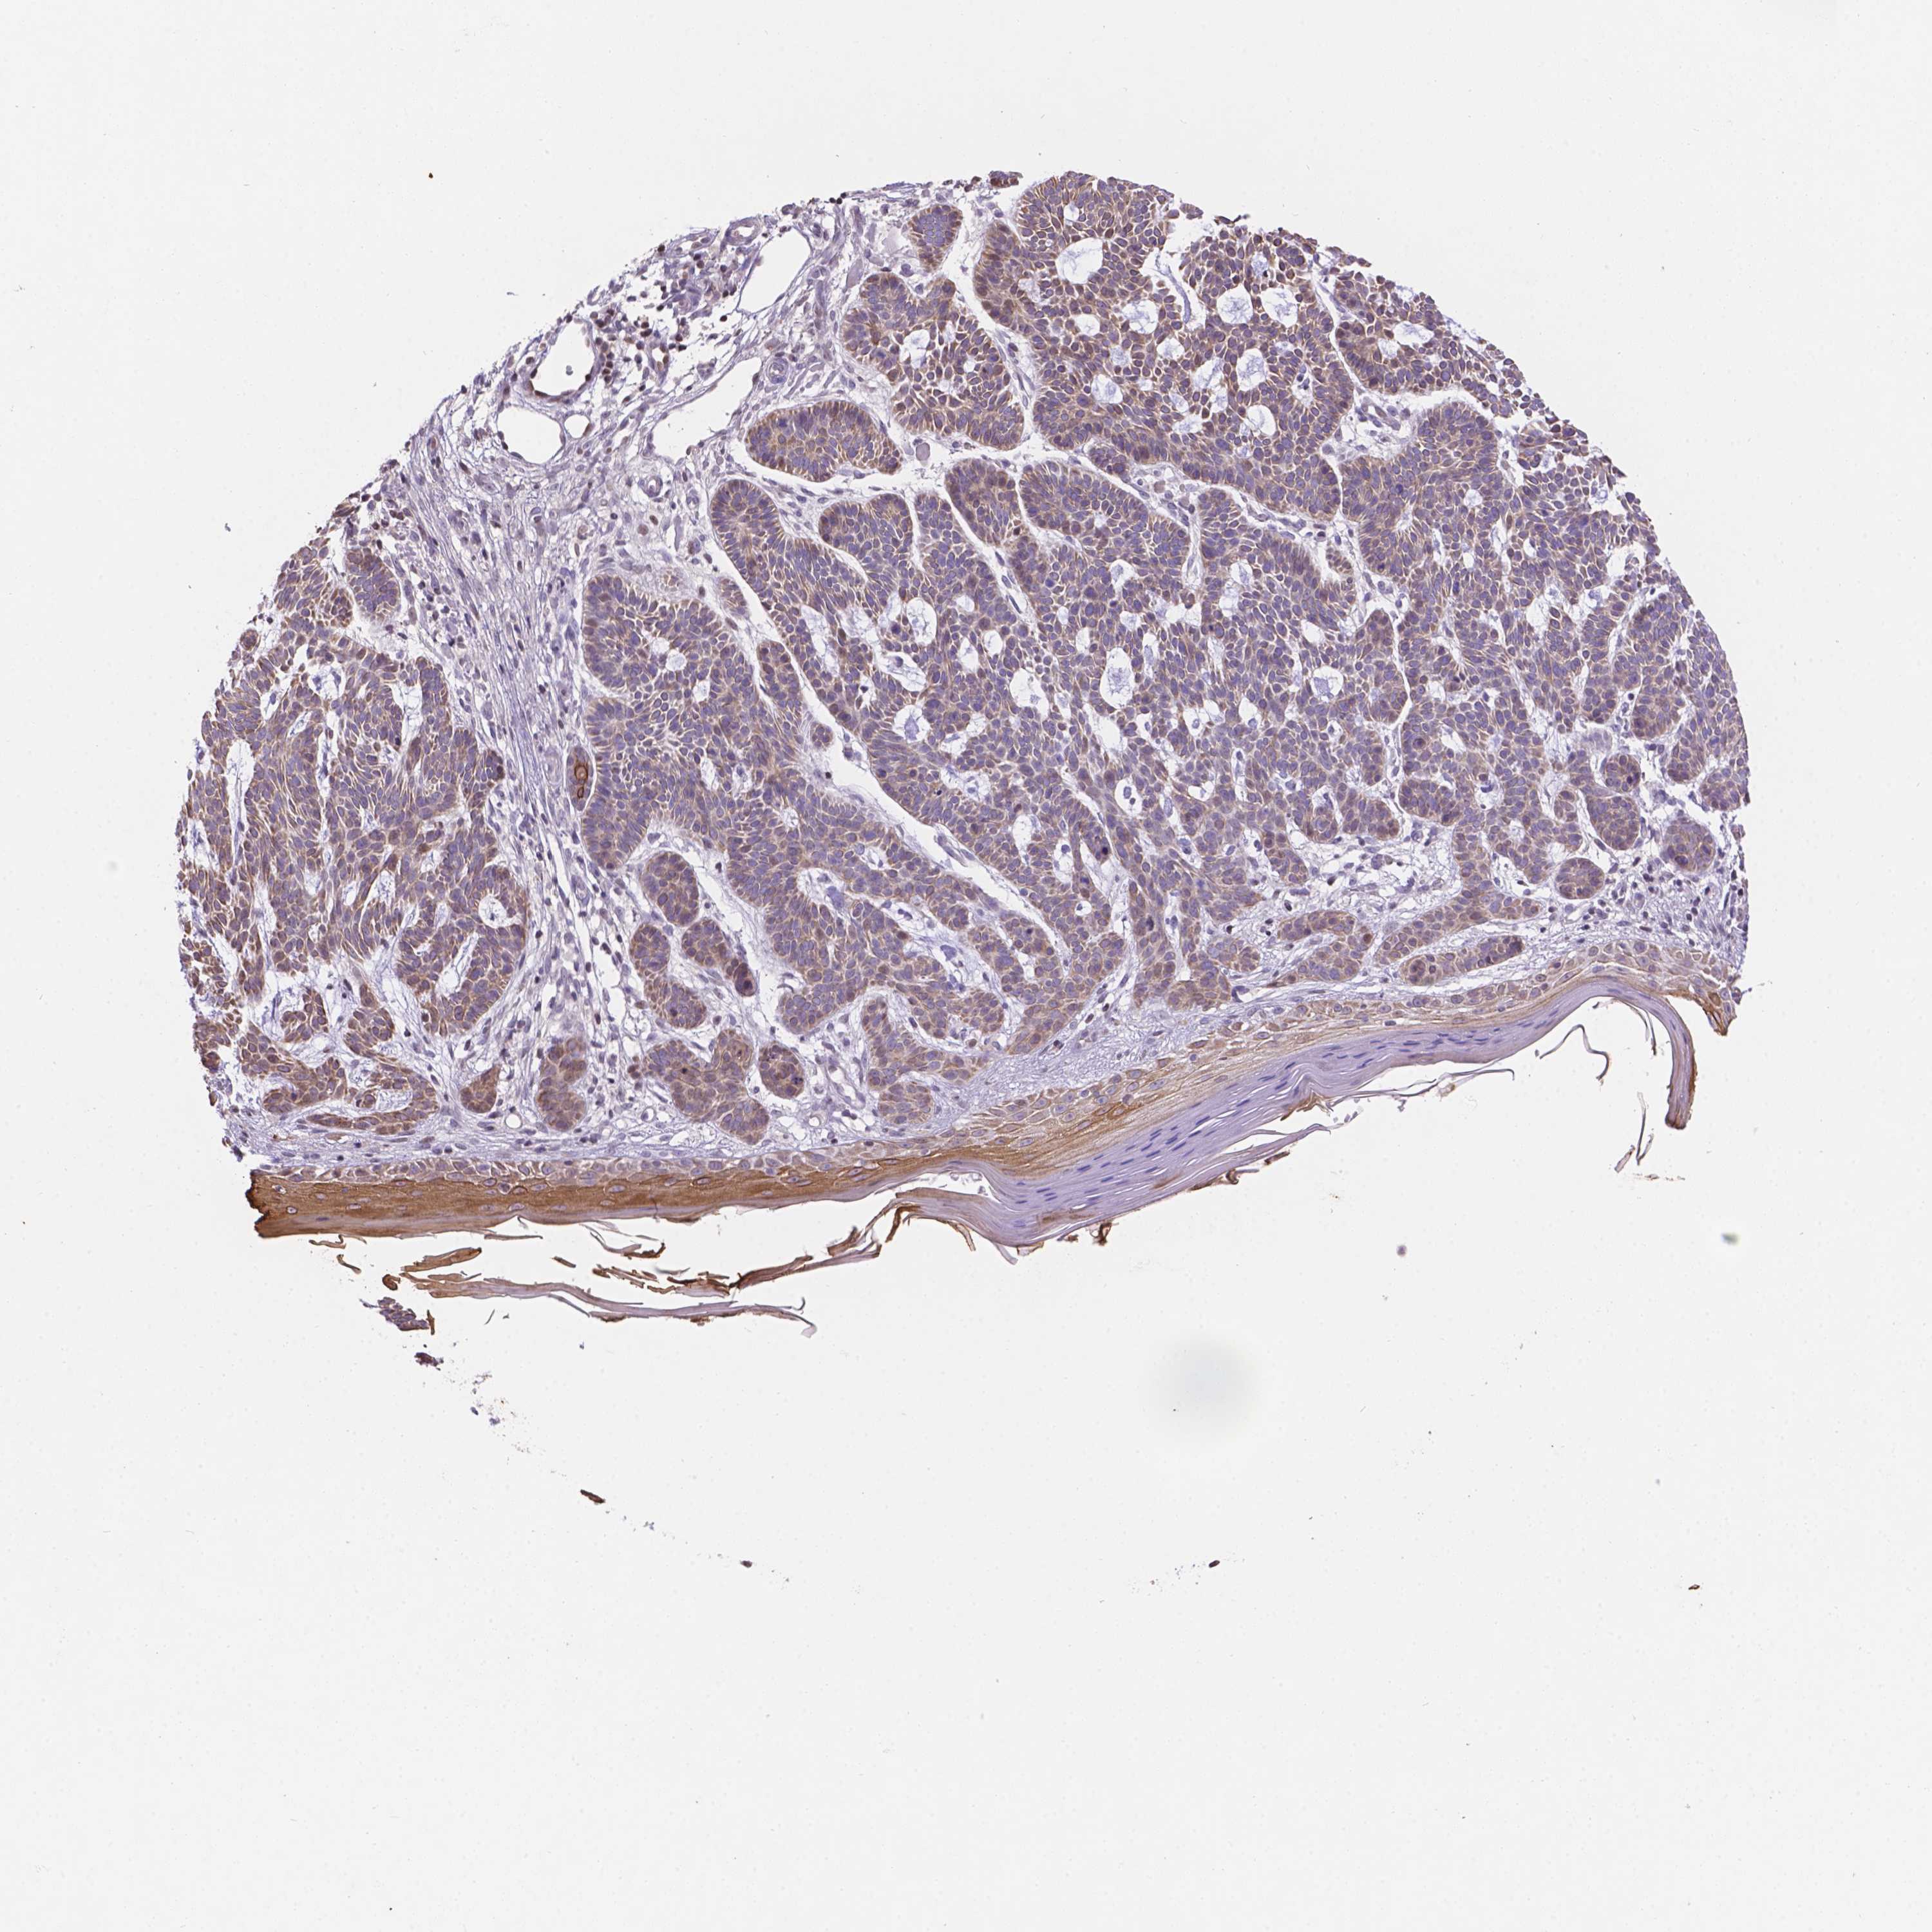

CANCER SKIN CANCER Show tissue menu

SKIN CANCER - Protein expressioni

A mouse-over function shows sample information and annotation data. Click on an image to view it in a full screen mode. Samples can be filtered based on level of antibody staining by selecting one or several of the following categories: high, medium, low and not detected. The assay and annotation is described here.

Antibody stainingi

Antibody staining in the annotated cell types in the current human tissue is reported as not detected, low, medium, or high, based on conventional immunohistochemistry profiling in selected tissues. This score is based on the combination of the staining intensity and fraction of stained cells.

Each image is clickable and will lead to virtual microscopy that enables deeper exploration of all samples and also displays staining intensity scores, fraction scores and subcellular localization as well as patient and tissue information for each sample.

Antibody HPA068172

Antibody HPA069843

Basal cell carcinoma

Squamous cell carcinoma, NOS